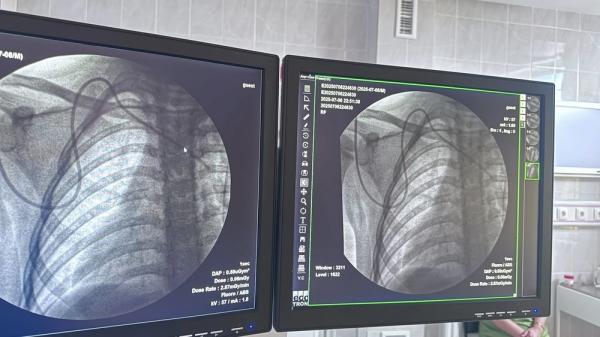

Впервые самостоятельно установили порт-систему ребенку с онкологическим диагнозом, сообщил 7 июля заведующий отделением детской онкологии и онкогематологии НЦОМиД Султан Стамбеков на своей странице в соцсетях.

«Если раньше мы проводили такие процедуры под наблюдением наших уважаемых коллег из России, то теперь мы освоили этот метод и применяем его в Кыргызстане самостоятельно. Совместно с Анваром Мавляновым и Тураббаевым Фаезбеком мы провели эту процедуру. Это не просто медицинская манипуляция — это шаг к более комфортному, безопасному и современному лечению наших маленьких пациентов», — рассказал он.